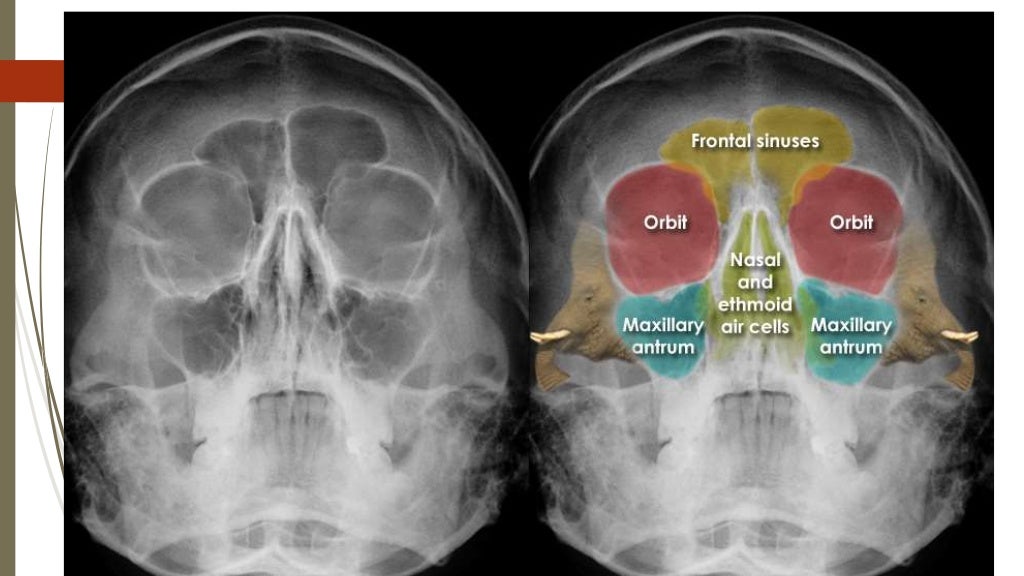

How To Read Facial Bone XRays By Peter Andre Soltau Jan2015 Facial Bones Orbit The viscerocranium consists of 14. the face skeleton includes 14 facial bones (6 paired and 2 unpaired) with specific anatomical landmarks and. the viscerocranium or facial bones supports the soft tissue of the face. what are the facial bones. The human skull comprises 22 bones, among which 14 facial bones form the front portion of the skull,.. Facial Bones Orbit.